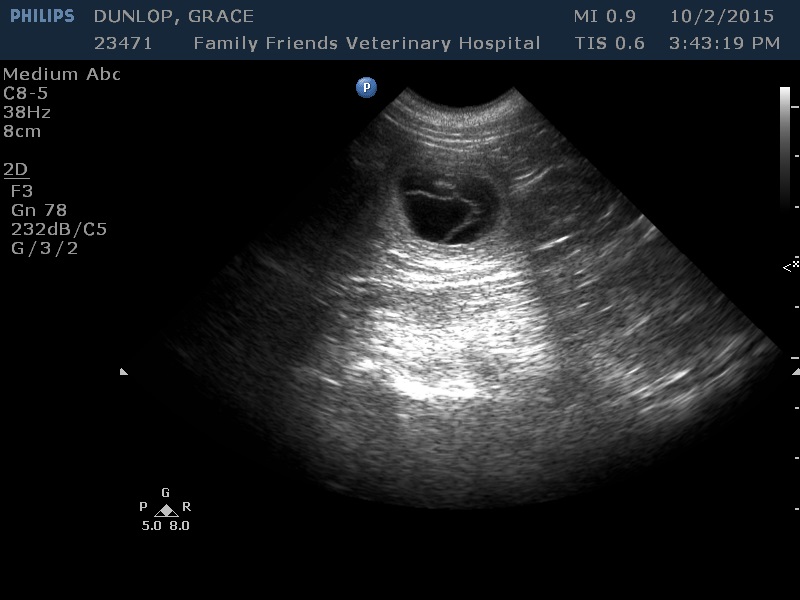

It’s a YES!!! He saw at least 8 babies on the Grace ultrasound. We are SO EXCITED BUT THE WAIT is going to be murder!! We have been trying for a year and a half and it appears the problem was poor Horace had an enlarged prostrate. Who would have ever guessed that at his young age. Hope will make sure he’s in tip top shape for future breeding so. I’m not taking any more Grace deposits, but am taking Rosalie ( Dark color babies I think) and Dottie ( red and white and black and white) all will give us fabulous colors, we love unique!!

I get Harlee off the bus a few times a week, we come to the park to play with the dogs and the kittens ( I took two of Harlees kittens that were at her moms house) it’s usually a little warmer and dryer by then so we have a good romp😀 Girls are always happy to see her. Rosalie is getting a belly about a week early which usually means lots of babies. I am SO GLAD we found this new vet in Grand Rapids. What a fabulous place, they do grooming, boarding, day care. Prices are reasonable and everyone SO NICE! If you’re in area you should try FAMILY FRIENDS VET HOSPITAL 6555 28th St 616.575.6520 Michigan State recommended them to my vet for reproductive services, turns out Rosalie ovulates late and we were giving up too early. Grace goes tomorrow for an ultrasound to see if she has babies. I honestly don’t know, one minute I think yes, then next minute no (sigh) I need to know😁 And the people who sent deposits are all eager to know!!! Stand by for NEWS!